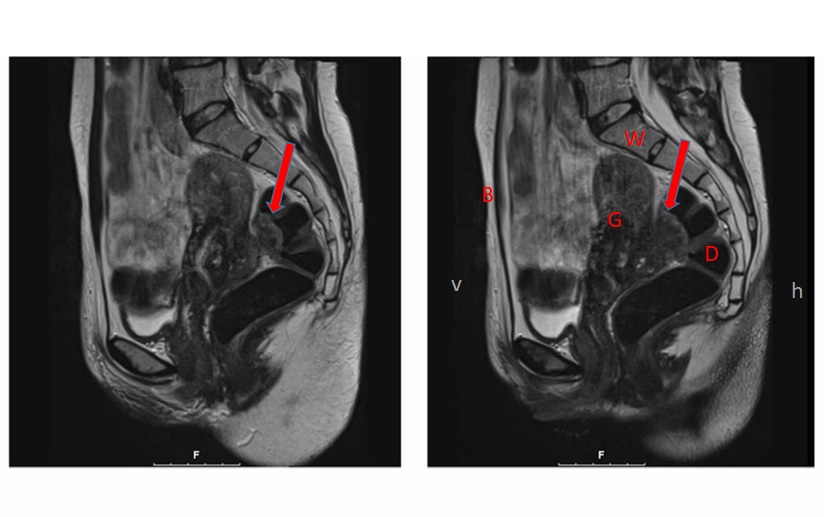

Endometriose betrifft jede zehnte Frau im gebärfähigen Alter. Diese gutartige chronische Erkrankung verursacht vor allem während der Regelblutung teils starke Bauchschmerzen und kann eine Rolle bei unerfülltem Kinderwunsch spielen. Dabei wächst Gewebe, das der Gebämutterschleimhaut ähnlich ist, ausserhalb der Gebärmutter im Bauch. Selten kann dieses Gewebe tief in andere Organe wie etwa den Darm oder die Vagina einwachsen (sogenannte tief-infiltrierende Endometriose). Oft wird dann eine Operation zur Entfernung der Endometriose nötig.

Weiter ergab die Studie: Frauen mit Endometriose hatten eine leicht erhöhte Neigung zu kleineren Kindern (Geburtsgewicht unter dem Durchschnitt) und zu Bluthochdruck während der Schwangerschaft. Ausserdem kam es etwas häufiger als gewöhnlich zu einer sogenannten «Plazenta previa», bei welcher der Mutterkuchen den Geburtskanal verschliesst.